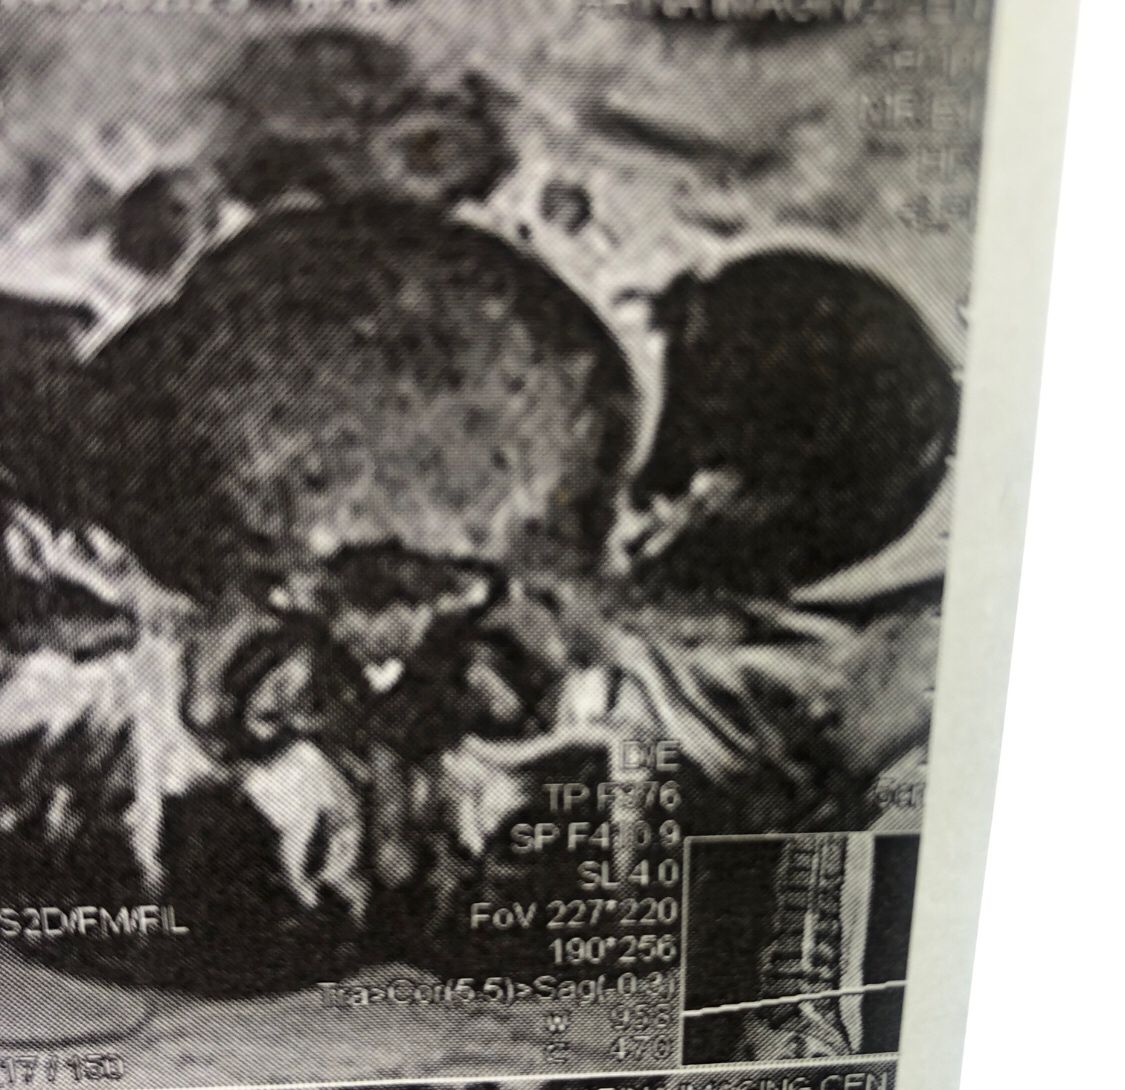

46 years old female patient presented to my clinic yesterday june 1/2025 with LBP and radicular L leg pain for several months which hasn’t responded to physio 2 neurosurgeons have visited her and didn’t suggest any surgery Neurological exam was unremarkable please see her mri/ emg/ncv and her huge tarlov cyst and possible L IVF L4-5 hyperbulge I ordered sacrum mri and ct scan and new emg/ncv and asked her with her sacral Ct scan and MRI first sees another two famous neurosurgeons and see if that large cyst is the reason for her pain if not i can work on her L4-S1 area Do you think her radicular pain can originate from her large cyst in sacrum? Do you consider surgery and removing her sacral cyst?